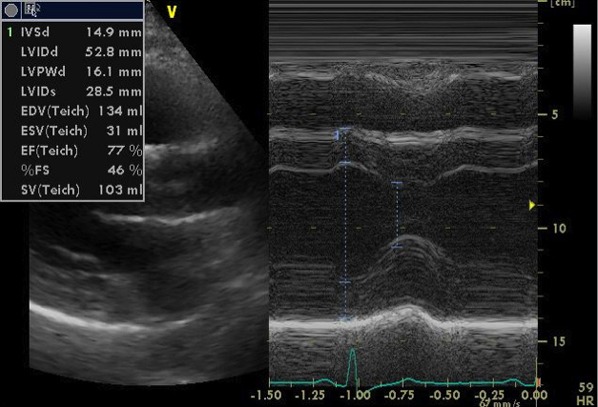

心エコー検査では、弁機能に異常なく、心嚢液の貯留はない。左房径(64mm)と左室径(60mm)は著明に拡張、左室は瀰漫性に壁運動の低下(EF=20%)。左室壁は中隔厚(18mm )、左室後壁厚(21mm)と共に肥厚しており、長年の左室圧負荷に加え、左室の収縮不全を認めることから、高血圧性心疾患に加え何らかの心筋疾患の可能性も否定できない。

心エコー画像1

心エコー画像2

心エコー画像3